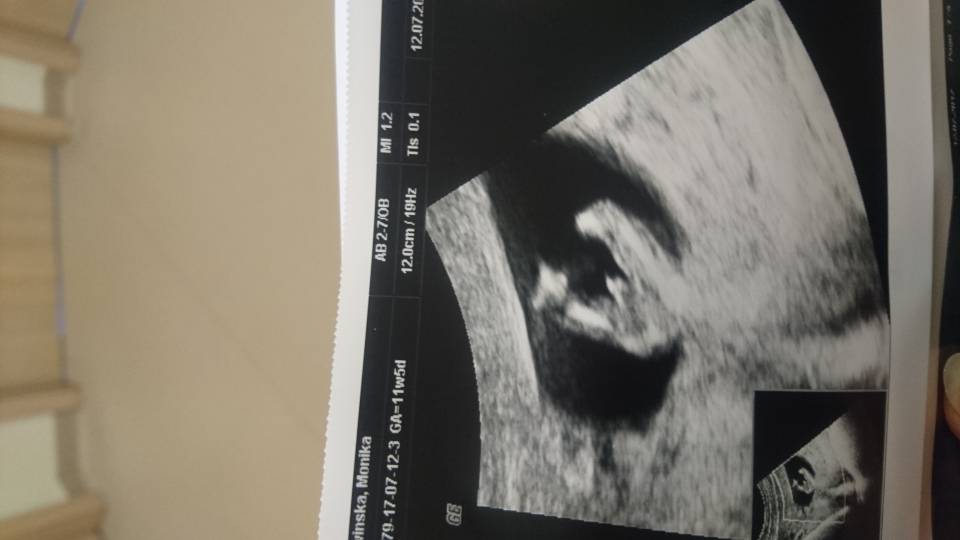

Zobacz załącznik 814979

Ja mam takie zdjęcie pupy a i tak się boję kupić typowo chłopięce :-)

Przy takim zdjęciu chyba nie masz powodów do obaw:)